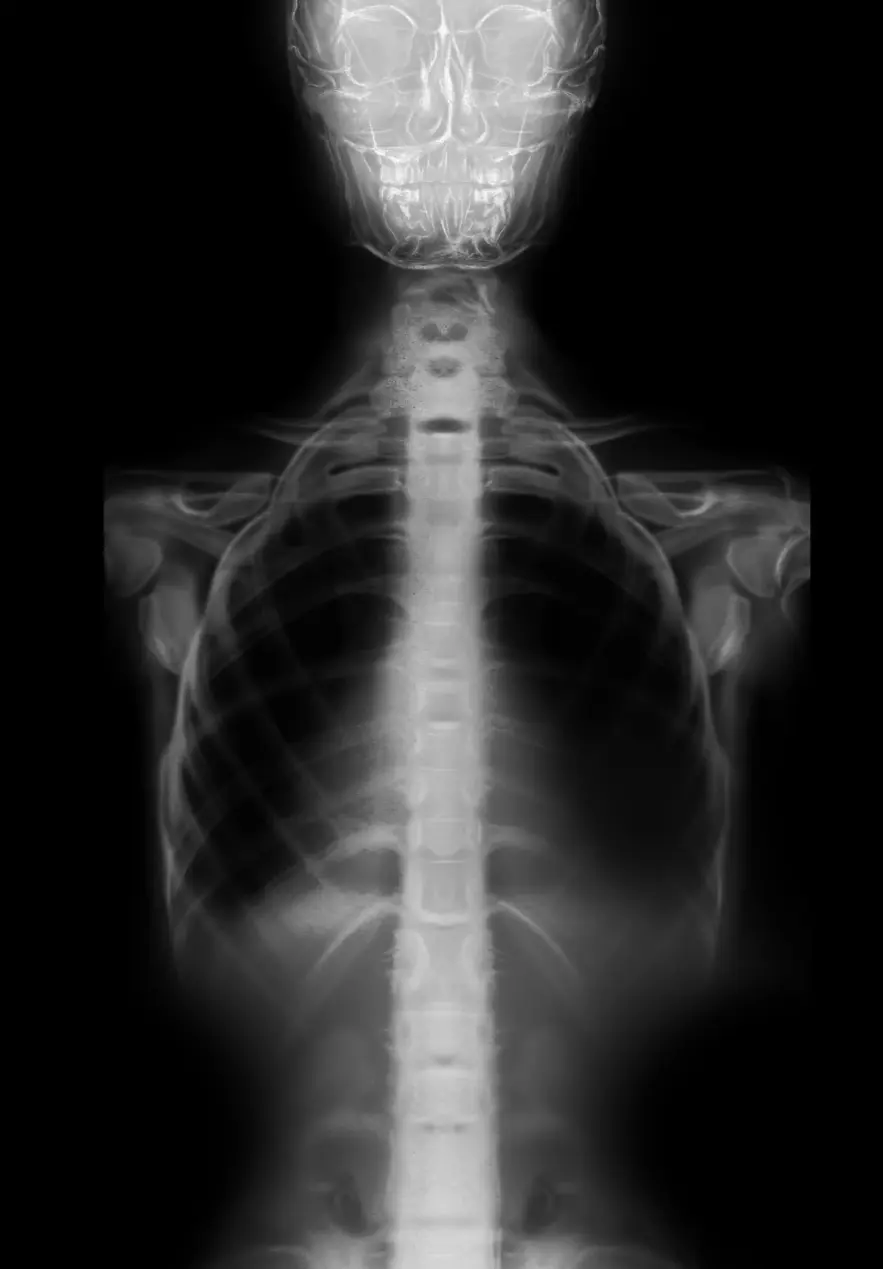

Antes

Después